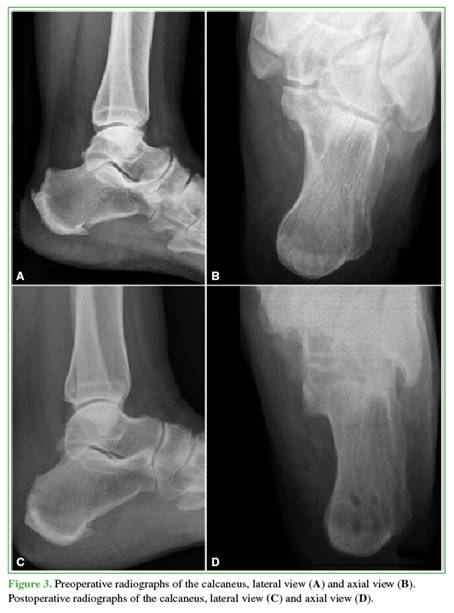

The retrocalcaneal bursa is resected, the diseased portion of the tendon is debrided, and Haglund’s deformity is resected using an oscillating saw (Figure 1). The healthy remnant of the Achilles tendon is then reinserted at the insertion site using the Achilles SpeedBridge™ double-row suture system. Finally, layered closure is performed (Figures 2 and 3).

Post-surgical Protocol